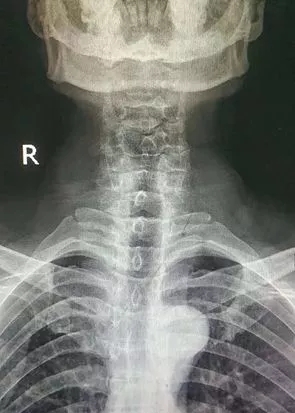

到医院后,经医生检查并结合影像学结果诊断,刘大叔颈7椎体压缩性骨折并椎管狭窄、颈椎间盘脱出、左侧肢体伴有瘫痪,急需颈椎手术治疗。

术前X片

颈椎是人的生命之枢,统领全身的血管和神经,颈椎同时伴多部位骨折很危险也很罕见。特别是术中螺钉穿行的部位旁边是为大脑提供血液的椎动脉,手术稍有不慎,都会引起严重后果,手术难度极高,这要求主刀医生必须拥有脊柱外科扎实的基本功和丰富的手术经验。医院副院长脊柱科首席专家谢军、脊柱科主任李伟雄等组成的医护团队,认真评估患者术前病情,经过会诊,制定详细的麻醉手术方案及术后的康复流程。与此同时,专家团队积极完善各种术前准备,择期在全麻下为刘大叔行颈7椎体次全切﹢椎管扩大﹢钛笼植骨融合前路﹢自锁钢板内固定手术。经过两个小时的紧张手术,专家团队克服了颈椎骨折、脱位、压迫脊髓椎动脉等巨大风险,术后患者肢体功能恢复良好,头脑清醒,没有出现任何其他并发症。